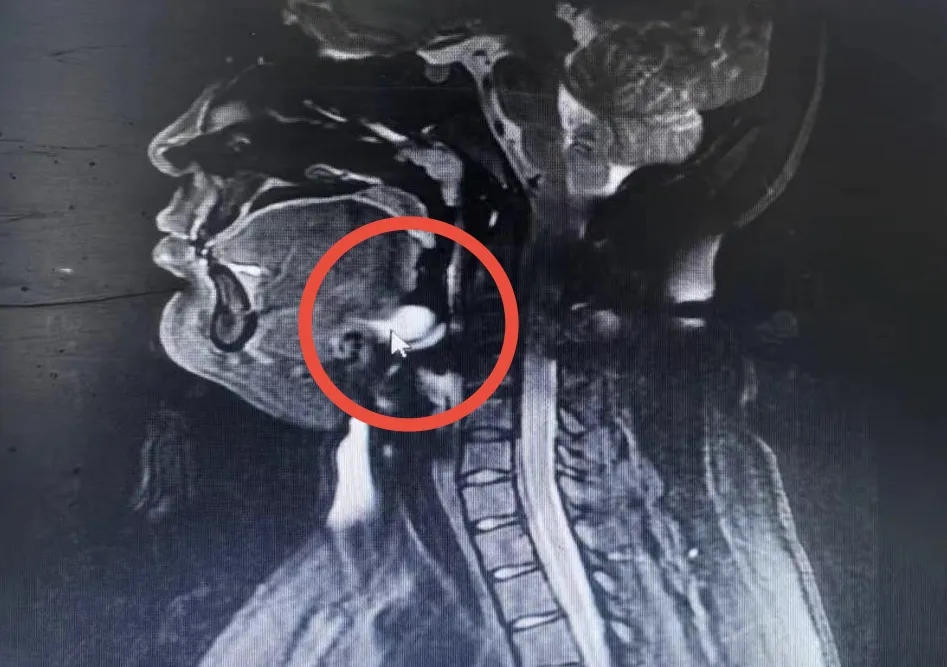

患者住院后,王芳副主任医师为患者完善各项术前检查,并组织全科医护人员进行术前讨论,认为甲状舌管囊肿是一种常见病,但是口内型的发病率相对较低;术前MRI检查(如上图示)可以明确诊断,但由于囊肿较大,位置较深,手术难度较大,且术后容易复。考虑到患者为青年女性,手术宜采用经口入路进行,可以达到颈部无痕的效果;术中应注意完整切除囊肿,尽量避免术后复发。